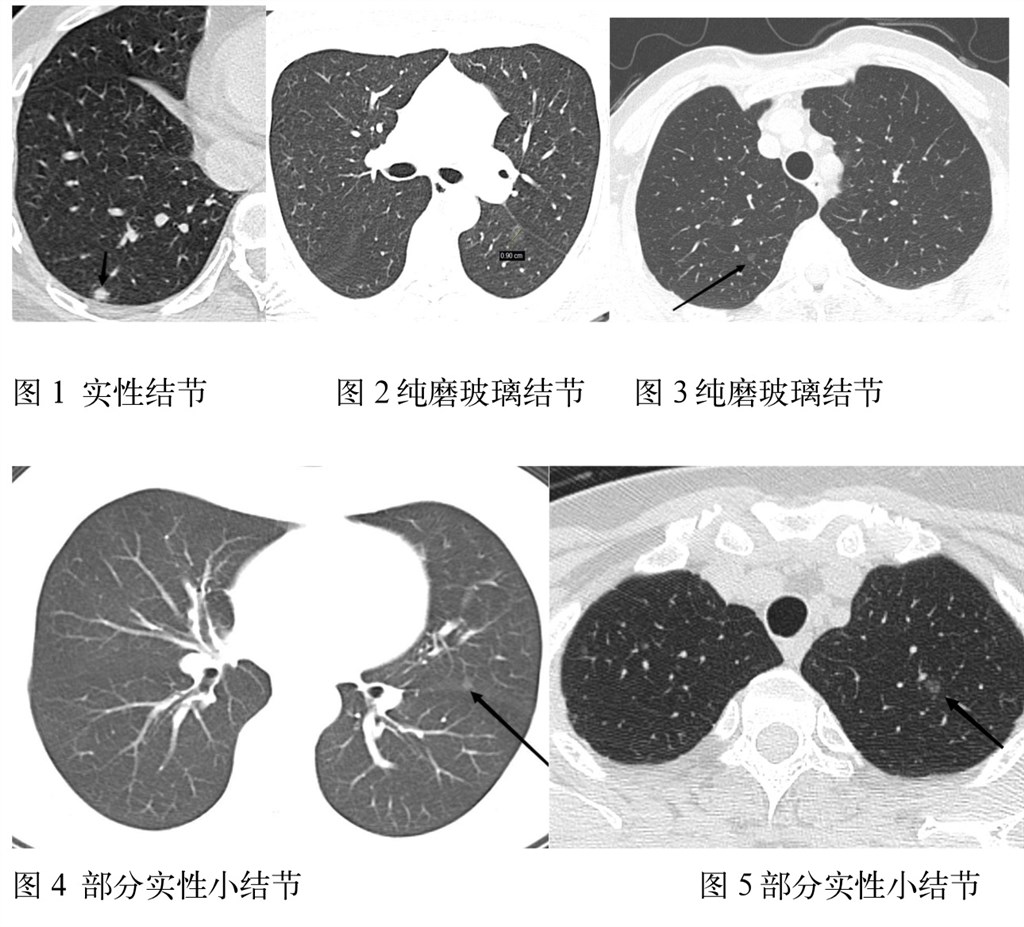

每个肺结节的影像表现有以下六部分组成:首先是大小:肺窗显示平均直径6;8;15及30mm都是比较关键的数值。大小30mm,恶性概率80%以上。密度(软组织、钙化类型、脂肪);形态(实性、非实性[磨玻璃]、部分实性[包含实性和非实性成分]);位置(叶、段、具体序列和层面);边缘(平滑、分叶、毛刺);增强程度。

因此结节的评估是一个多参数的综合评价。比如:磨玻璃密度结节,边界模糊提示良性可能大,如炎性渗出或肺泡内出血等;边界清楚锐利实性结节提示良性可能;实性结节,边缘毛刺及棘状突起,提示肿瘤可能大。需要和之前的CT片进行对比,尤其是那些符合基线调查(6mm;8mm;15mm)的病例,病灶大小增加超过1.5mm视为有生长变化。恶性征象:密度不均匀,分叶,短而细密毛刺,胸膜凹陷,血管增粗、卷入、集束,淋巴结肿大,胸水,骨质破坏。增强扫描:良性病变轻-中度强化(血管瘤及硬化性血管瘤等除外),恶性病变中度以上强化。

再有就是纯磨玻璃结节不要紧张,一般3omm像枣子那麽大才考虑恶性可能的!我们高度警惕应该是随访中逐渐出现了实性成分的,也就是部分实性结节直径≥8mm或实性部分12个月内平均直径增大1.5mm(体积>2mm3)逐次增加则要缩短检查间隔,需要考虑是浸润性病变,连续动态的观察至关重要,有些肺小结节就像川剧变脸一样,只是一个反派的角色扮演而已,所以表演者只是脸变,身材体型变化不大,连续的随访就能鉴别变化所以至关重要。这种明显变化的情况下建议手术切除。